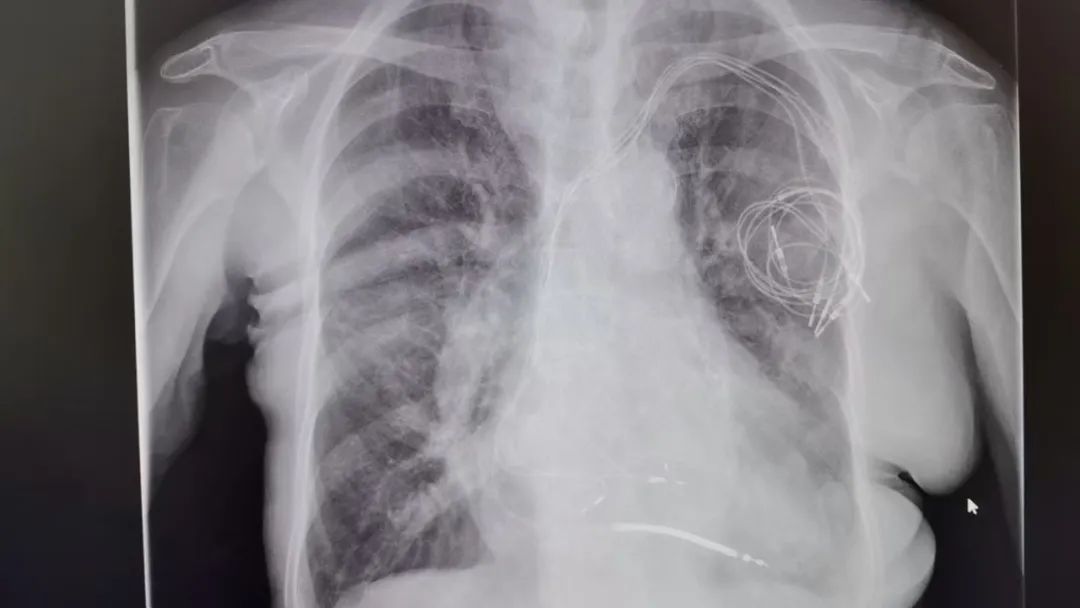

术前电极导线在体内的状态

造影提示锁骨下静脉闭塞

考虑到患者年龄较高,起搏器电极植入时间较长,电极导线和血管壁及心肌组织的粘连程度较重,使用传统的简单工具拔除或徒手拔除,不仅手术难度很大,同时会增加患者的手术风险。